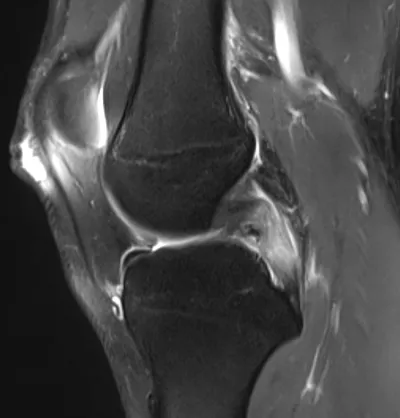

PCL Radiology Images

Browse 3 medical images tagged with pcl. This collection includes various imaging modalities for medical education and reference.

- This collection contains 3 radiology images related to pcl, including various imaging modalities such as X-rays, MRIs, CT scans, and ultrasound images commonly used in medical diagnosis and education.